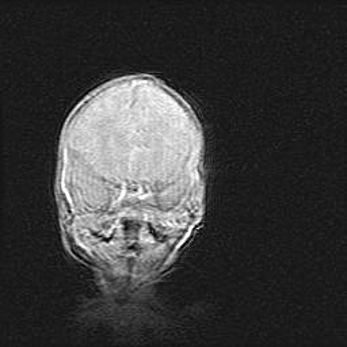

Лейкомаляция с кистозно-глиозной дегенерацией головного мозга.

Возраст: 2 месяца 25 дней

Вес: 6400 г

Окружность головы: 40 см

Срок гестации: 41 неделя

Лейкомаляцию относят к ишемически-гипоксическим повреждениям головного мозга, диагностируемым у новорожденных. При лейкомаляции в головном мозге обнаруживают очаги некроза, возникшие после тяжелой гипоксии и нарушения кровотока. В процессе морфогенеза очаги проходят три стадии: 1) развития некроза, 2) резорбции и 3) формирования глиозного рубца или кисты. Перивентрикулярная лейкомаляция (ПЛ) встречается примерно в 12% случаев среди новорожденных, обычно – у недоношенных детей, причем, частота ее зависит от массы, с которой младенец появился на свет. Наибольшее число малышей страдает лейкомаляцией, если масса при рождении 1500-2500 г.